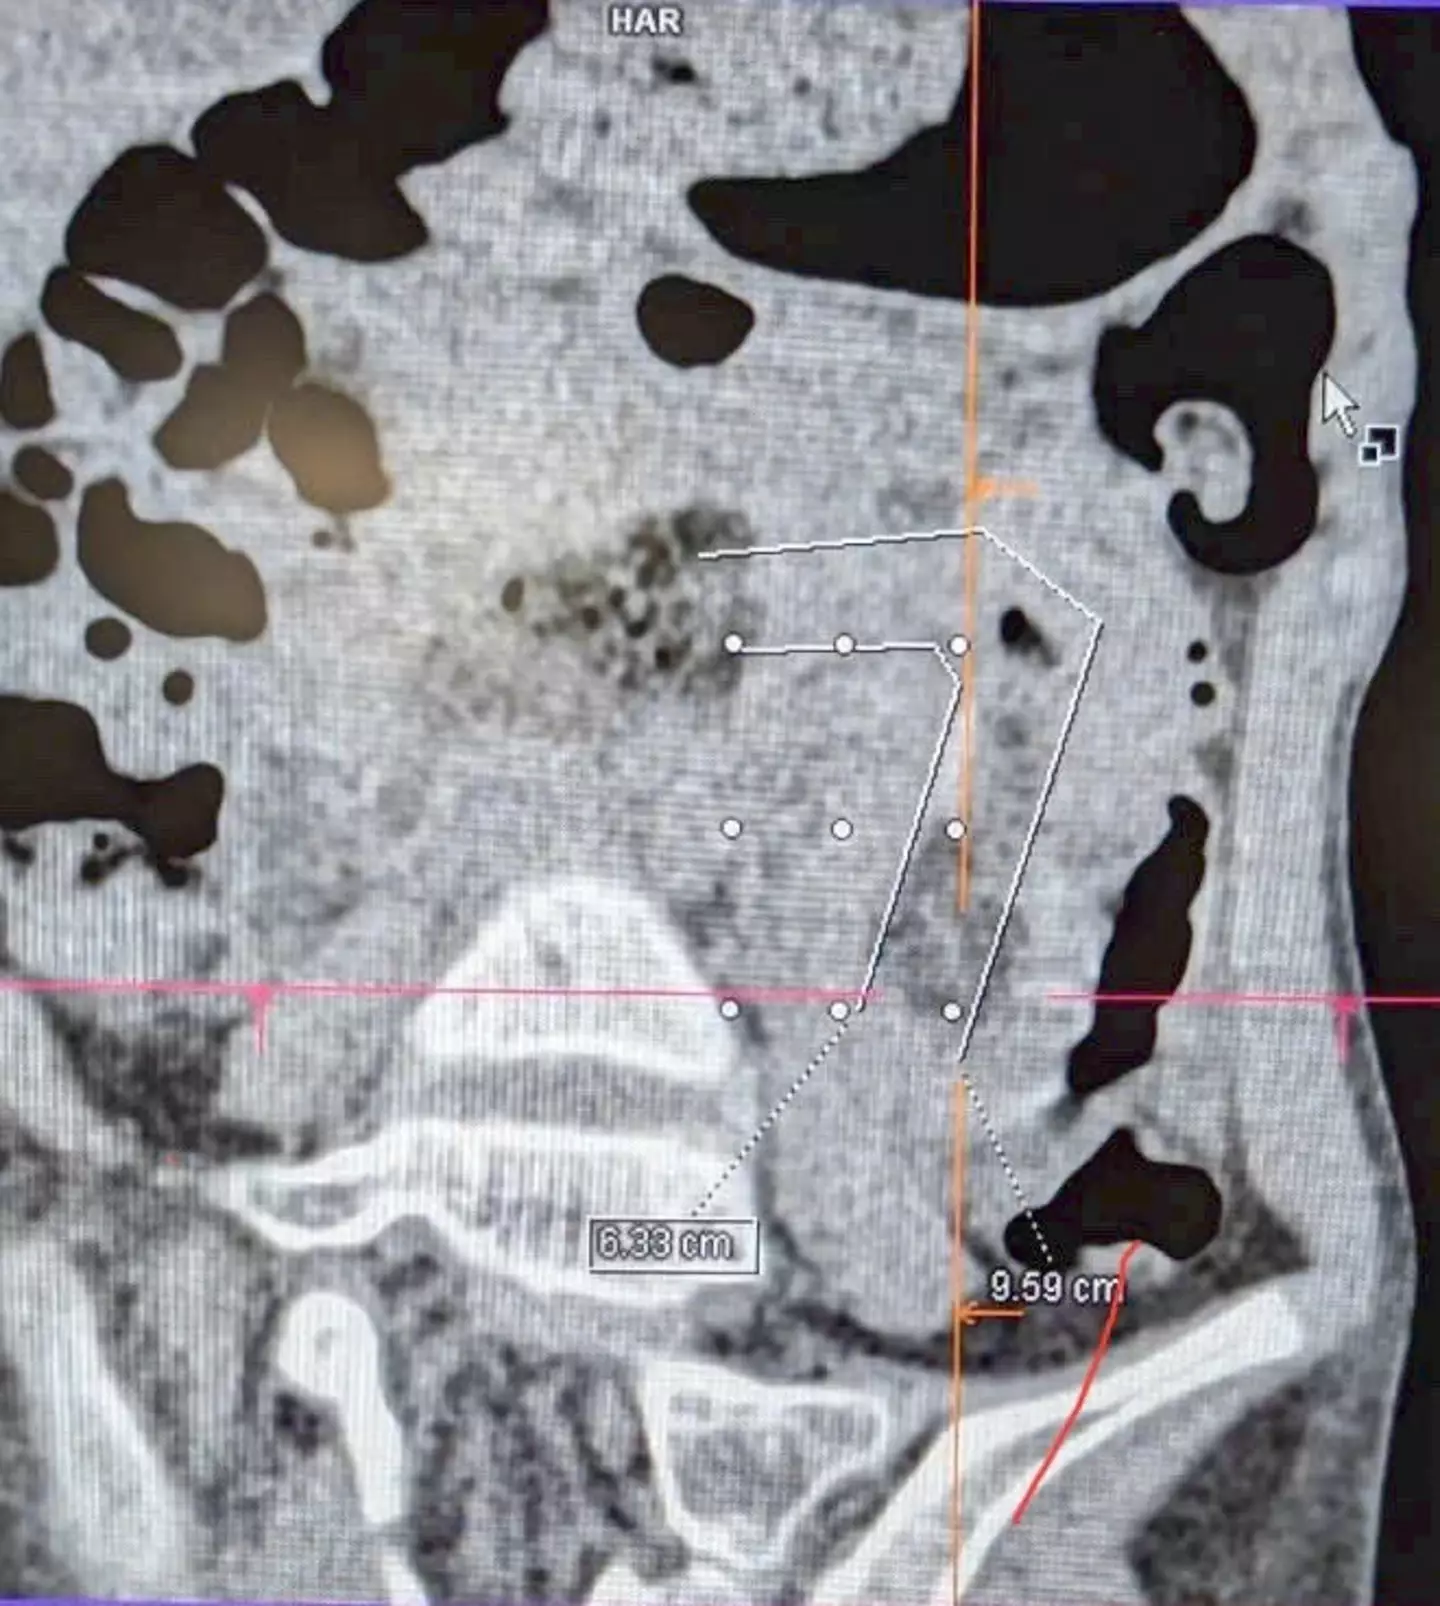

General Surgery, Gastroenterology, and Imaging specialists discovered a hairball of almost one meter long, tightly coiled from her stomach down into her small intestine.

The mass was causing ‘both intestinal obstruction and volvulus, creating a life-threatening situation’, as per the press release.

After a three-hour laparoscopic surgery and a gastrointestinal endoscopy, the hairball, which was ‘braided like a rope’, was removed.